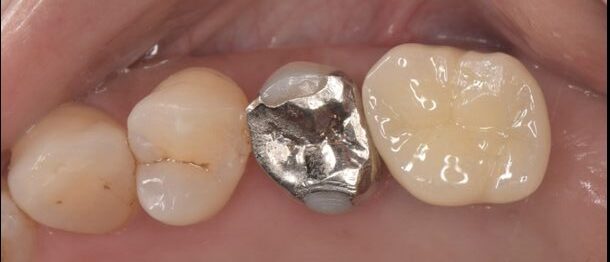

Before

左上の大臼歯が破折しており、保存が不可で抜歯を行い2ヶ月治癒を待ちました。